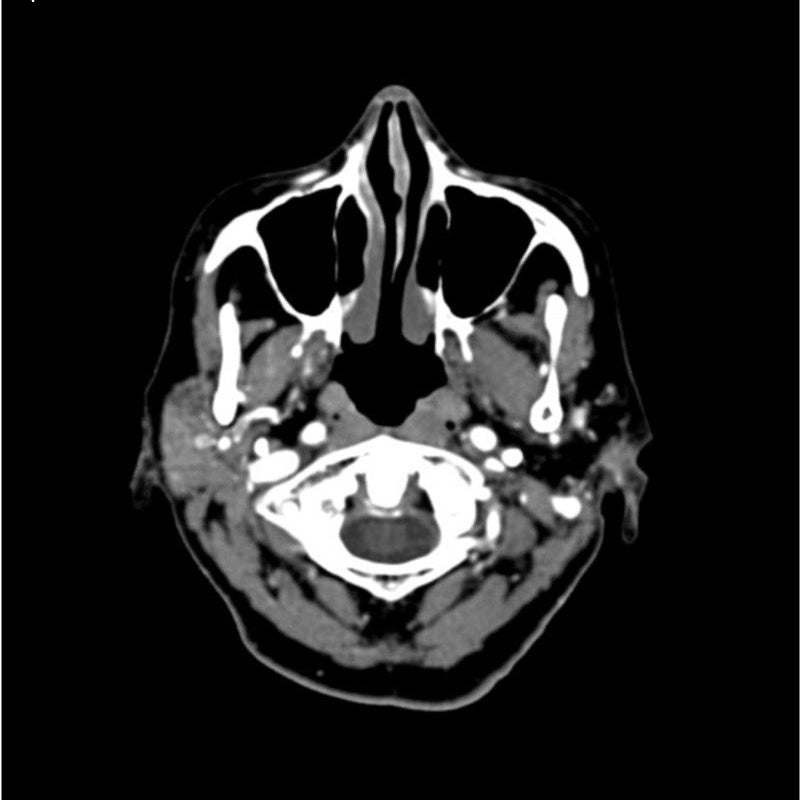

This phantom simulates a contrast medium enhanced head in arterial phase (CT angiography). The neck and upper thorax are included up to the aortic arch and the fifth thoracic vertebra. The vertex is included until approximately 0.5 cm below skin level. The thoracic phantom section excludes shoulder and back parts that are typically not part of CTA examinations. The interncal carotid artery has calcifications on both sides with moderate stenosis on the right side. Otherwise, the phantom has no significant vascular pathologies.

The phantom can be used in CT (including CBCT) to evaluate and optimize CTA imaging performance and post-processing applications such as vessel segmentation, including AI-enabled applications. It is also nicely suited for training purposes. The phantom provides a detailed and realistic simulation of vascular structures, soft and bone tissue, including small details such as lymph nodes. Air voids are filled with a cellulose-polymer composite of approx. -160 HU.

Realistic simulation of head and neck vessels up to the aortic arch, bone and soft tissues.

Calcifications of the internal carotid artery at the carotid bifurcation on both sides with mild stenosis on the right side.